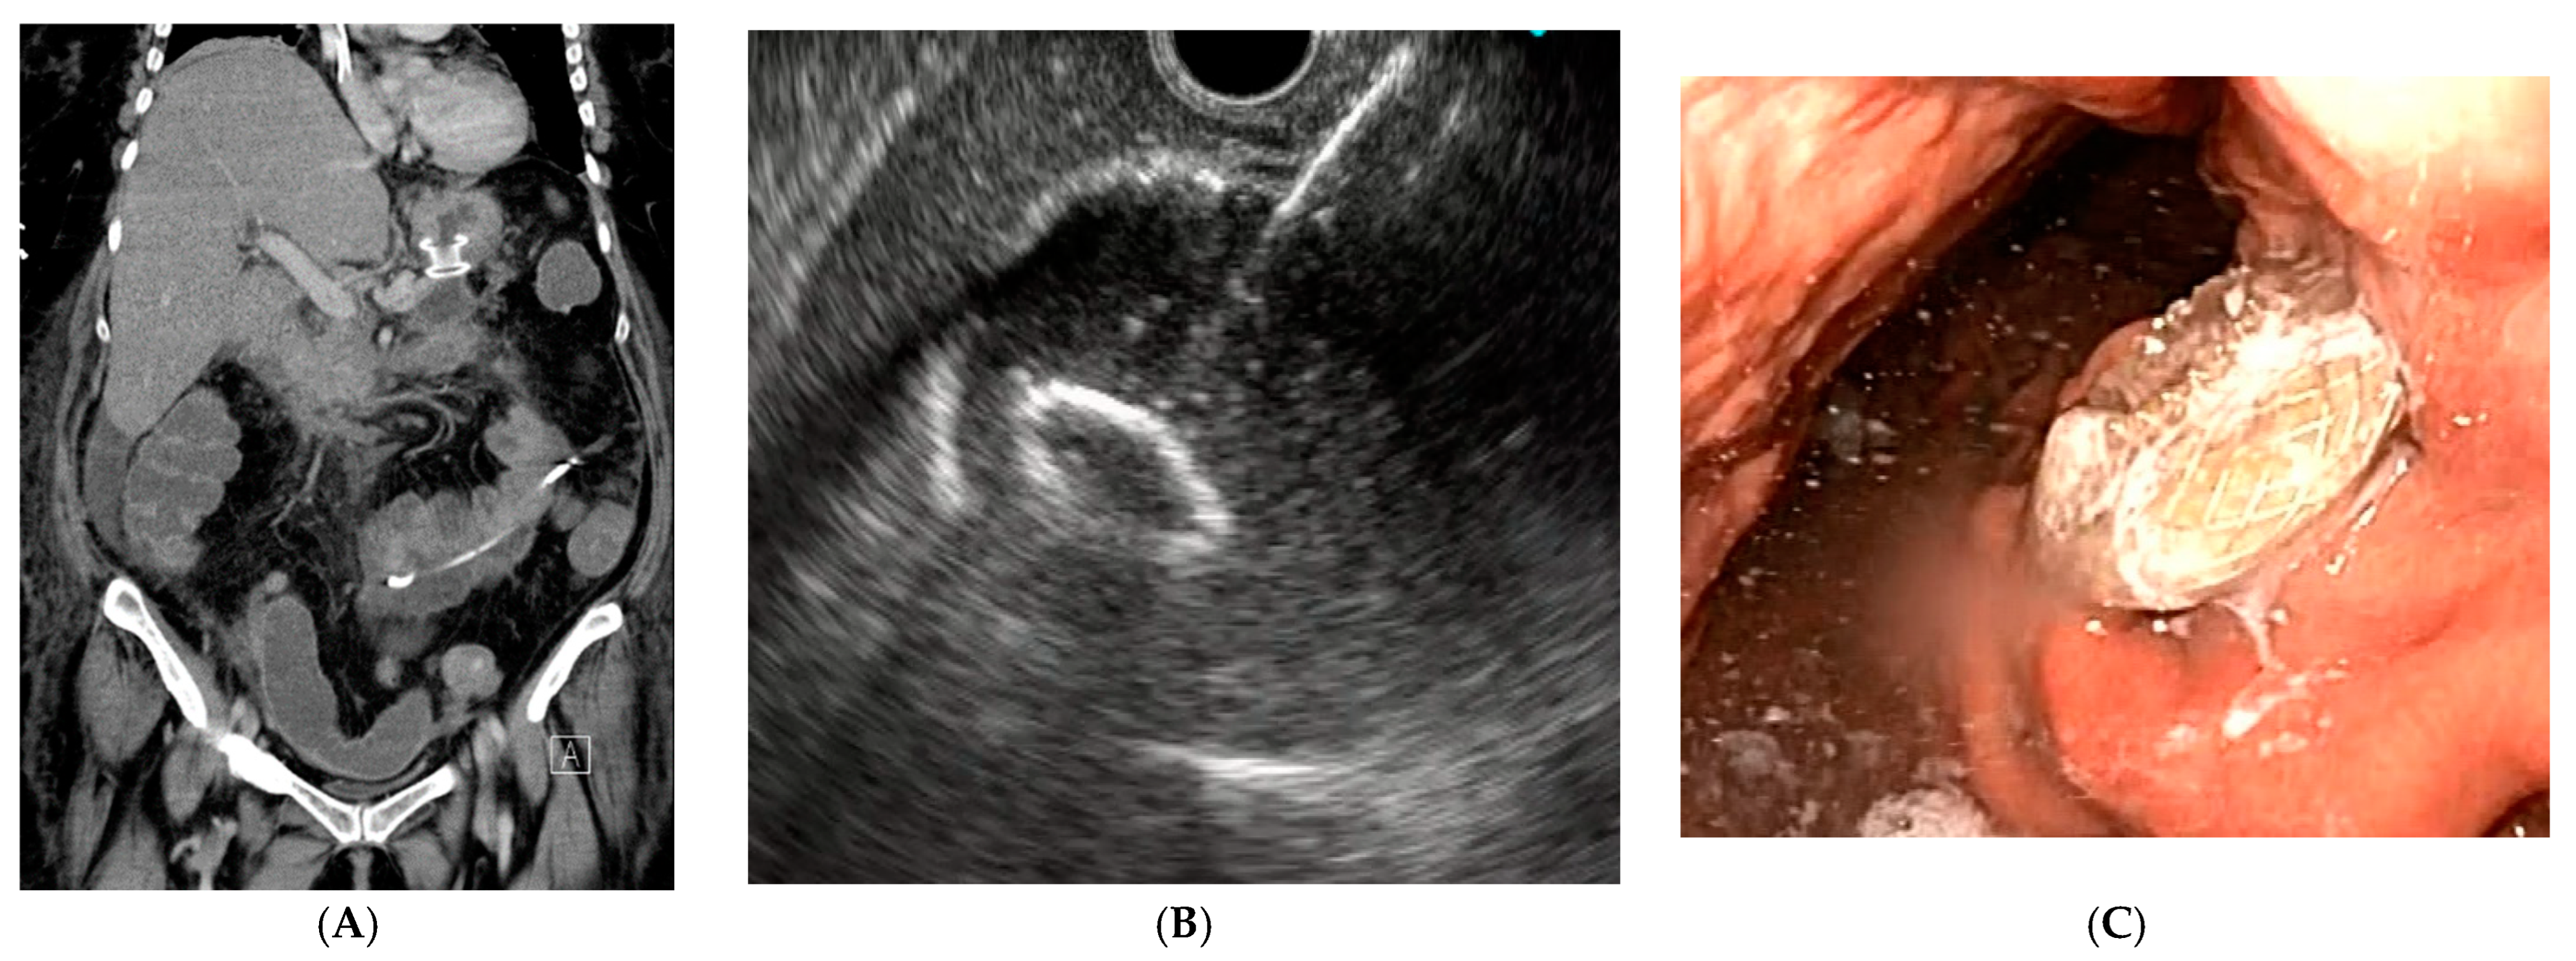

2. Biliary Obstruction

3. Gastric Outlet Obstruction (GOO)

- Cominardi, A.; Tamanini, G.; Brighi, N.; Fusaroli, P.; Lisotti, A. Conservative management of malignant gastric outlet obstruction syndrome-evidence based evaluation of endoscopic ultrasound-guided gastroentero-anastomosis. World J. Gastrointest. Oncol. 2021, 13, 1086–1098. [Google Scholar] [CrossRef] [PubMed]

- Vanella, G.; Bronswijk, M.; van Wanrooij, R.L.; Dell’Anna, G.; Laleman, W.; van Malenstein, H.; Voermans, R.P.; Fockens, P.; Van der Merwe, S.; Arcidiacono, P.G. Combined endoscopic mAnagement of BiliaRy and gastrIc OutLET obstruction (CABRIOLET Study): A multicenter retrospective analysis. DEN Open 2023, 3, e132. [Google Scholar] [CrossRef]